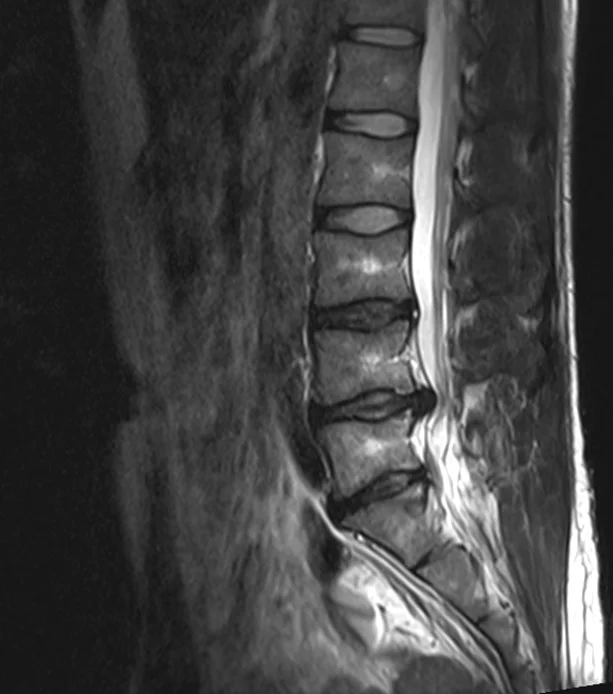

Eilisen tilanne magneetissa. Oikeasssa kankussa/lonkan seudulla ollut keväästä asti särkyä ulkokierrossa ja selällään on ollut vaikea maata. Tai oikeastaan mahdotonta niin että kankku ei olisi pienessä jännityksessä. Välillä kipu säteilee nilkkaan. Kuitenkin tuon kanssa on pystynyt elämään ja liikkumaankin kohtuullisesti.

Olen ollut sitä mieltä että kipu on lihasperäistä (tulehduksesta esim. ja liiasta autossa ja tuolilla istumisesta toimistotyöstä johtuen) ja olen sitä mieltä edelleen. Oikeastihan tuo pullistuma (joka on vasemmalla puolella) on kuvissa pahentunut, mutta vasemmalle puolelle ei kipua ole käytännössä ole ollut enää kevään jälkeen. Yksi selkä, yksi elämä. Kuvissa lokakuu 2012, maaliskuu 2013 ja joulukuu 2013.

Lekurille oli tunnin aika ja tuossa kerkesi jo oikeasti tutkia melko hyvin, lääkärillä oli aikaa kuunnella ja selittää teoriaa melko ymmärrettävästi. Tosin laskukin oli sellaiset 250€. Tuo oma pullistuma on jäätävän kokoinen kun sitä katsoo päältäpäin otetusta kuvasta. Siltikin on mielenkiintoista miten vasemmallapuolella ei ole oireita, vaikka pullistuma on siellä ja painaa selvästi hermoa. Oli myös lohdullista kuulla että jos tuo leikataan, ei kauheasti tartte ottaa stressiä siitä että pullistuma uusiutuu. Nimittäin ei ole enää sen jälkeen mitään mitä pullistua ulos. Kuvissa näkee miten ylemmässä välissä on ollut tuo annulusvaurio 9kk ajan, eikä sekään ole siitä mihinkään korjaantunut.